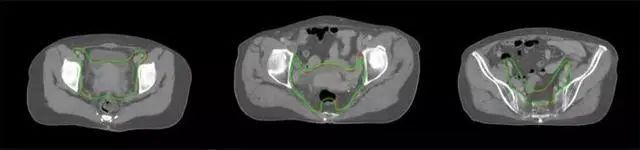

放射治療,簡稱放療,是治療腫瘤主要手段之一,利用放射線破壞照射區(qū)(靶區(qū))的細(xì)胞,使腫瘤細(xì)胞停止分裂直至死亡,醫(yī)生通常把放射治療形象的比喻為“打靶”,放療前精準(zhǔn)勾畫腫瘤靶區(qū)范圍是腫瘤放射治療的關(guān)鍵步驟。傳統(tǒng)的靶區(qū)勾畫醫(yī)生會(huì)根據(jù)患者多張CT、MRI影像片憑借經(jīng)驗(yàn)進(jìn)行,比較耗時(shí),治療的病人數(shù)量也有限,且靶區(qū)勾畫缺少行業(yè)統(tǒng)一的規(guī)范和標(biāo)準(zhǔn),無法達(dá)到同質(zhì)化,勾畫精確度不理想。

技術(shù)原理

基于深度學(xué)習(xí)人工智能的放療靶區(qū)智能勾畫技術(shù)和自動(dòng)計(jì)劃技術(shù),基于全面的市場調(diào)研和臨床專業(yè)意見,采用獨(dú)創(chuàng)的基于小樣本量的人工智能算法,實(shí)現(xiàn)放療靶區(qū)和危及器官的快速全自動(dòng)勾畫。

產(chǎn)品優(yōu)勢

縮短至幾分鐘內(nèi)便可完成,大幅提升了放療效率,且人工智能平臺(tái)完成的靶區(qū)勾畫可基本滿足臨床醫(yī)生需求,專家只需審核時(shí)細(xì)微調(diào)整,可顯著提高靶區(qū)勾畫的規(guī)范化及精準(zhǔn)度,讓放療智能化,標(biāo)準(zhǔn)化??筛采w食管癌、鼻咽癌、直腸癌、宮頸癌、肺癌等多種病種。